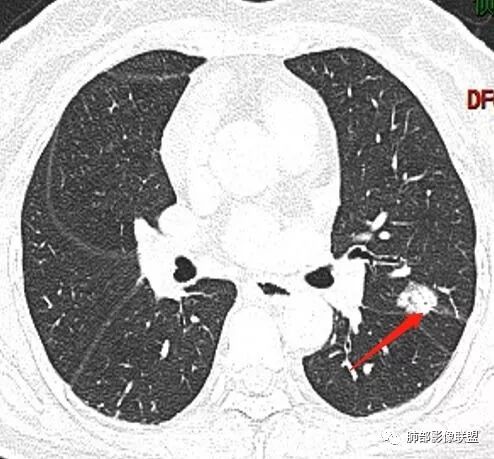

马宁强:考虑肉芽肿性病变,隐球菌可能彭君:左肺上叶舌段混合毛玻璃密度结节 边缘清 有分叶毛刺 斜裂胸膜凹陷征 考虑腺癌可能王秀仙:左肺上叶结节,部分边缘磨玻璃清晰,有分叶毛刺,支气管通过并扩张,其外侧小叶间隔不规则增厚,胸膜牵拉,考虑腺癌。鉴别慢性炎症。田园晚风:左肺上叶多个小结节融合呈分叶状,可见叶间裂牵拉,考虑腺癌张帅:左肺上叶后段结节,内可见支气管穿过,病灶周围有少许毛刺,病灶边缘有浅分叶,对叶间胸膜有牵拉,部分位置呈对叶间胸膜推移。考虑为恶性病变,腺癌?。杨泽锋:混合型磨玻璃结节,边缘有膨隆、有凹陷,明显的胸膜牵拉,考虑腺癌可能大;内部支气管通畅、似乎有鬼脸征,所以鉴别隐球菌Lotus:病灶内部有结节感,这个大小似乎是次级肺小叶的大小,考虑炎性,有冠位最好了。但是胸膜牵拉有些恶性提示心包右侧软组织密度影考虑心包隐窝Yiren Sishui(厶水伊人):叶间裂有膨隆有凹陷,考虑恶性,腺癌可能

徐婕:同意恶性腺癌可能岁月:女,56;空泡,分叶毛刺,牵拉线,胸膜凹陷征,有强化,浸润性腺癌。THINKER:左舌见结节,膨胀为主,部分收缩,分叶丶短丶硬毛刺,牵拉斜裂,有小空泡,支气管穿行,有强化,常规腺癌丽:左肺上叶近胸膜下结节,胸膜牵拉,边缘膨隆,并可见深分叶及毛刺,内有空泡,增强后可见强化,倾向腺癌淘时光:混合磨玻璃结节,实性部分较多,内见支气管穿行,腺癌首先考虑了…☀:左肺上叶结节影,实性,边缘分叶征,其内可见空泡,部分膨胀生长,局部叶间裂牵拉上移,叶间裂光滑增厚,首先考虑肿瘤黄棘:左肺上叶结节,边缘彭隆, 周围磨玻璃影边界清,内部可见扩张支气管,叶间胸膜牵拉,考虑腺癌心灵鸡汤:左肺上叶舌段近斜裂处混合性结节,以实性成分为主,有分叶、毛刺,牵拉邻近叶间、脏层胸膜,增强有强化,影像学上看偏恶性,分类LU-RADS 4C类,MIA浸润性腺癌可能,鉴别肉芽肿性病变、隐球菌,请老师指点!THINKER:这个如果是腺癌,应该是IAC了,过MIA了,个人看法,罗老师一切∮随缘:左肺叶裂胸膜下结节,边缘收缩弱,周围有GGO,边界清楚,形态欠规则,其内似有支气管穿行,增强扫描轻度均匀强化,考虑1肉芽肿性病变(隐球,炎性假瘤)2:浸润性腺癌Clover:考虑腺癌,实性为主混合有少许边界清晰ggo,边缘膨隆,其内支气管气象不规则,有收缩力。Coke with ice:还有一个疑问请教一下:这个是混合磨玻璃结节还是实性结节?个人倾向于后者。心灵鸡汤:有部分磨玻璃Coke with ice:实性结节周围GGO初学者:实性,周围有毛玻璃晨:有浅分叶,有毛刺,有叶间裂牵拉,内有囊泡,考虑腺癌。初学者:稍等,我等会开电脑看,但是感觉和你们一样,感觉是一个典型病例来着Coke with ice:这个人我也倾向于腺癌。但是诊断腺癌还有一个比较疑惑的地方,肺窗病变密度显示比较实,但是纵隔窗病灶范围明显比肺窗小,腺癌可以解释的通吗?张小兵:混合磨玻璃结节,内见支气管穿行,分叶,胸膜牵拉从凹陷处进入,腺癌首先考虑小微:

下面这个如何考虑?

wonderful:

那么小不转移吧,另外一个结节?

不是转移。毛玻璃,原发可能,需要随访

边界清GGO?随访是个好主意

一般临床处理是立刻开左边的,在胸膜旁的很好定位。右边随访